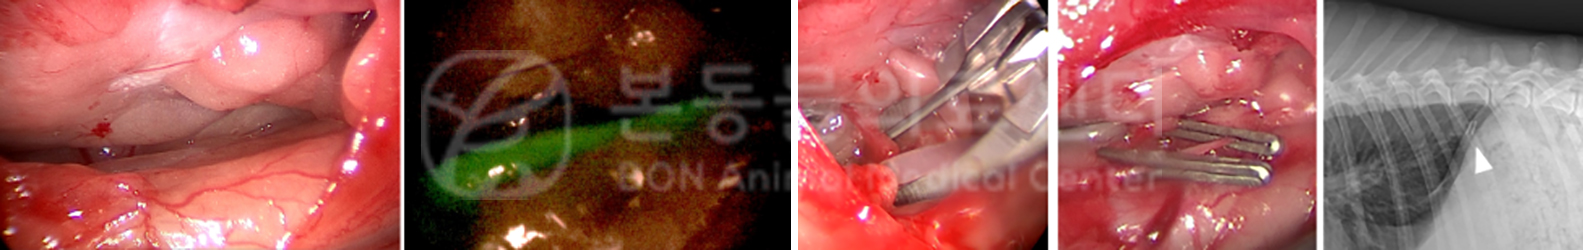

특히 수술적 접근은 적정 치료 시기에 시술 시 가장 확실하게 유미흉을 해소할 수 있는 방법입니다. 본동물의료센터에서는 수술적 흉관 결찰을 위해 CT 림프관 조영술 이외에도 형광 내시경 시술을 이용하고 있습니다.

CT 림프절 조영술을 통해 흉관의 주행 양상을 우선 확인 후,

실제 흉관 결찰 시에는 특정 물질(indocyanine grred) 을 주입 하여 형광 내시경 시술 시(near-infrared fluorescent lymphangiography) 림프관이 뚜렷하게 확인되기 때문에 흉관 결찰 시 시술 성공률을 높일 수 있는 장점이 있고, 실제 본원에서 적용 시 림프관도 잘 보일 뿐만 아니라, 술 후 유미흉도 재발하지 않았습니다.